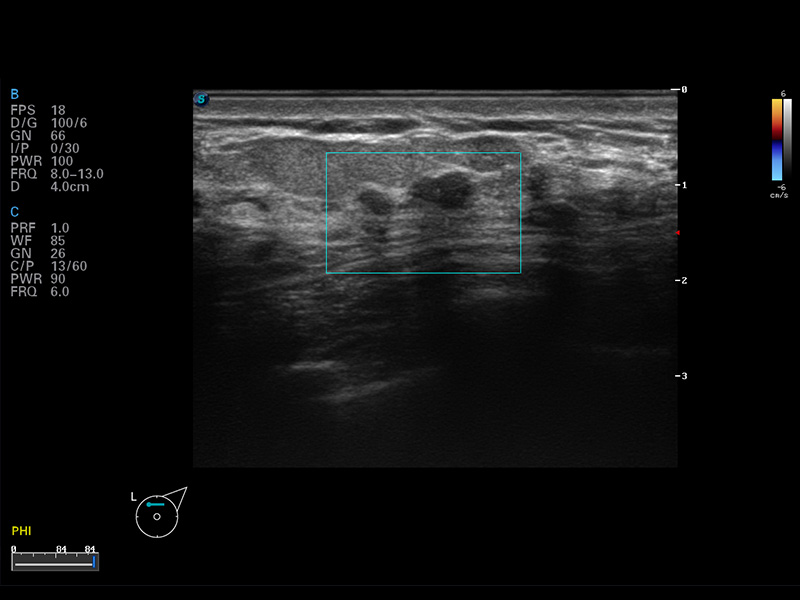

S8 EXP便携式彩色多普勒超声诊断仪是银河集团官网研发的高端全身应用型便携彩超。高通道的VIS平台融合可视化(Visual)、智能化(Intelligent)和人性化(Smart)的特点,配以银河集团官网自主研发生产的探头大家族,使您能够快速、准确的获得病人信息,提高工作效率的同时减轻疲劳。

成像技术

μ-Scan微米成像

谐波成像

空间复合成像